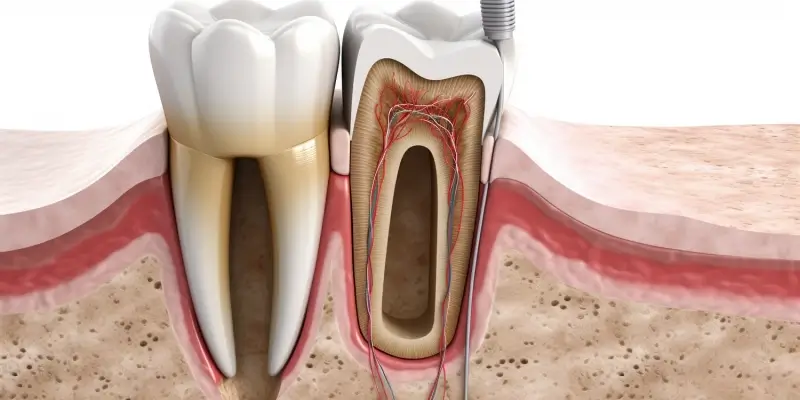

Najlepszy gabinet stomatologiczny w Warszawie powinien oferować szeroki wachlarz usług, które odpowiadają potrzebom różnych pacjentów. Wśród podstawowych usług znajduje się profilaktyka, czyli regularne przeglądy oraz czyszczenie zębów, które pomagają w utrzymaniu zdrowia jamy ustnej. Kolejną istotną usługą jest leczenie próchnicy, które obejmuje zarówno wypełnienia, jak i leczenie kanałowe. W przypadku pacjentów z problemami ortodontycznymi, dobry gabinet powinien oferować także aparaty ortodontyczne oraz konsultacje dotyczące korekcji zgryzu. Stomatologia estetyczna to kolejny ważny obszar, który obejmuje wybielanie zębów, licówki czy korony porcelanowe. Dodatkowo, coraz więcej gabinetów oferuje usługi związane z implantologią, co pozwala na skuteczne uzupełnienie brakujących zębów.

Nowoczesne technologie odgrywają kluczową rolę w dziedzinie stomatologii, a ich zastosowanie w najlepszych gabinetach stomatologicznych w Warszawie znacząco podnosi jakość świadczonych usług. Współczesne gabinety często wyposażone są w zaawansowane urządzenia diagnostyczne, takie jak cyfrowe rentgeny, które pozwalają na szybsze i dokładniejsze obrazowanie zębów oraz tkanek otaczających. Dzięki temu lekarze mogą precyzyjniej diagnozować problemy oraz planować leczenie. Kolejną innowacją są skanery wewnątrzustne, które umożliwiają tworzenie trójwymiarowych modeli zębów, co znacznie ułatwia proces projektowania aparatów ortodontycznych czy koron. Warto również zwrócić uwagę na systemy CAD/CAM, które pozwalają na szybkie i precyzyjne wykonanie uzupełnień protetycznych bez konieczności wykonywania tradycyjnych odcisków. Dodatkowo, nowoczesne gabinety często korzystają z technologii laserowej, która może być stosowana w leczeniu próchnicy, wybielaniu zębów czy chirurgii stomatologicznej, minimalizując dyskomfort pacjenta oraz czas rekonwalescencji.